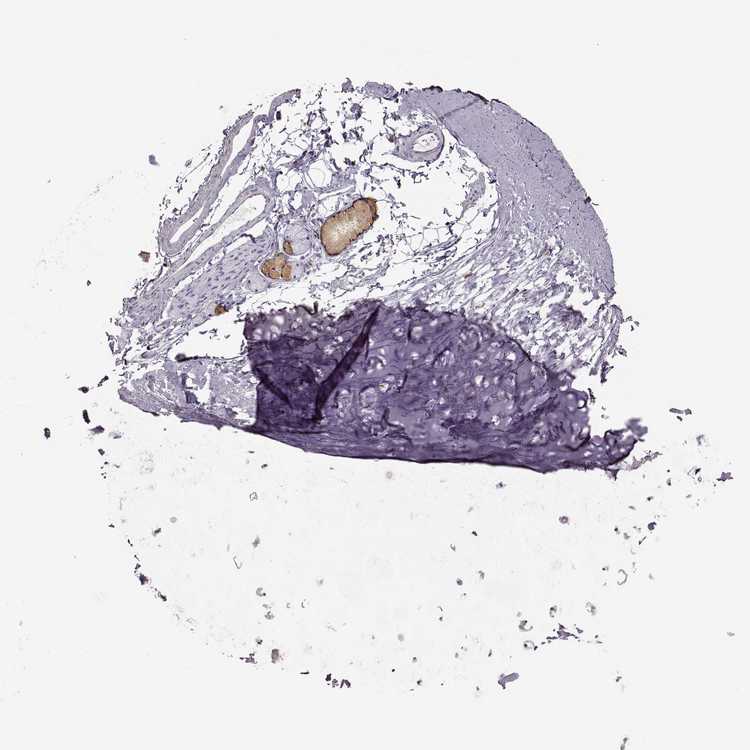

SOFT TISSUE 1 - Antibody stainingi

Antibody staining in the annotated cell types in the current human tissue is reported as not detected, low, medium, or high, based on conventional immunohistochemistry profiling in selected tissues. This score is based on the combination of the staining intensity and fraction of stained cells.

Each image is clickable and will lead to virtual microscopy that enables deeper exploration of all samples and also displays staining intensity scores, fraction scores and subcellular localization as well as patient and tissue information for each sample.

Antibody HPA001079

Chondrocytes Not detected

Fibroblasts Not detected

SOFT TISSUE 2 - Antibody stainingi

Peripheral nerve Not detected